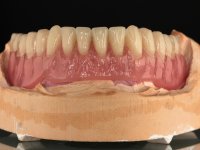

Two dental implants were planned in the CBCT scan, in the area of the inferior canines. The dental extractions were performed and, simultaneously, the alveolar crest was flattened and the implants were placed. Three issues were considered while implant placement: parallelism of the axis, same height of the implant’s neck, and same position in the coronal plan. This 3D insertion is essential to have a good retention of the overdenture in the future. Patient’s removable denture was fixed in the dental lab, to include the extracted teeth, and a soft-tissue relining was done over the healing abutments. After the osseo-integration period, a first impression was done with an open-tray and a doble-mix technique. This dental impression allowed the production of screwed wax-rims and an individual tray for a functional impression. A second impression, final, was done with an individual tray with a monophasic silicone. The occlusal wax-rims were correct in the mouth according to the full denture guidelines. Special care was taken with the occlusal vertical dimension and the support in the soft-tissues. A silicone bite registration material was used to better defined the intermaxillary relations. Teeth set-up was done in the dental lab with the selected tooth color. Due to the fact that the base was screwed to the dental implants, the teeth set-up was functionally evaluated in the mouth. Another silicone bite registration material was used to allow final occlusal adjustments. Finally, the locators were screwed and the retention nylons were selected according to the patient needs.